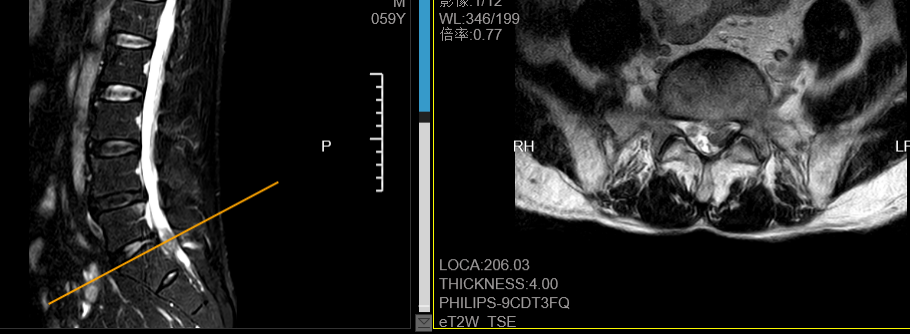

近日,在广东省人民医院(下称“省人医”)帮扶下,我院骨科一区利用椎间孔镜技术,为患者微创手术经后路镜行腰椎间盘髓核摘除消融术,术后疼痛马上缓解,次日下地行走,患者及家属表示由衷的感谢。